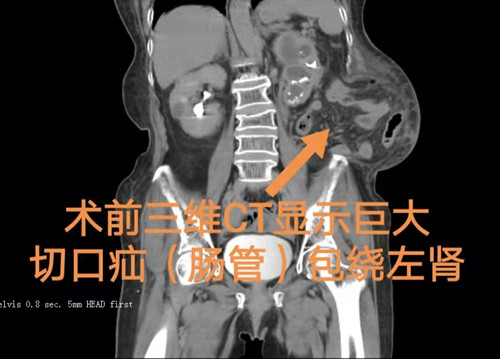

泌尿四科杨科主任介绍,何奶奶5年前因左肾感染并萎缩,在外院拟行肾切除手术,当时因手术难度大未能切除感染肾且术后并发了腹壁巨大切口疝,近年来多次求医,包括大型三甲医院就诊,一直未能得到有效治疗,慕名到泌尿外科四病区就诊,其腹壁巨大切口疝导致肠管、脾脏包绕肾脏周围,十分罕见,术前拟行左侧输尿管支架植入术备肾造瘘术的方案,术中因多次输尿管支架植入失败改肾造瘘术,穿刺造瘘如何避雷是首要考虑的问题,从术前CT来看,患者存在理论上的穿刺通道,因患者术中变动体位后,肾脏、脾脏、肠管相互挤压,穿刺通道建立难上加难,穿刺通道如何避开如肠管、脾脏、胸膜和大血管等重要的脏器,十分考验术者穿刺技术和勇气,患者精准定位完成穿刺造瘘成功后为下一步切除脓肾和巨大切口疝处理创造了有利的条件。(泌尿外科四病区 李铁求 杜丘)